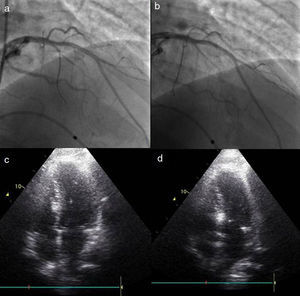

O procedimentoA intervenção inicia-se por uma coronariografia, com identificação da artéria alvo, habitualmente a primeira septal que se ramifica na porção basal do septo, sendo visível nesses vasos a presença de milking sistólico (Figura 1a). Por vezes a septal alvo pode originar-se de uma diagonal, da circunflexa ou mesmo da coronária direita, o que não aconteceu na nossa população. A avaliação da anatomia coronária, da facilidade de acesso ao vaso alvo e do seu calibre, permite a escolha do material a utilizar. Foram usados habitualmente cateteres guia Judkins e EBU de 6F, fios guia BMW® ou Pilot 50® (Abbott Vascular, Santa Clara, Califórnia, EUA) e cateteres de balão over the wire Apex Flex® (Boston Scientific, Natick, MA, EUA). Privilegiou-se a via femoral para favorecer uma maior estabilidade durante a cateterização coronária. Na presença de lesões coronárias significativas e com indicação para revascularização, consideramos que esta deverá ser efetuada primeiro e a ASA protelada para um segundo tempo, após reavaliação das queixas. Num doente da nossa população a origem da septal alvo relacionava-se com uma lesão da descendente anterior, ficando o seu posterior acesso provavelmente comprometido pela colocação do stent, pelo que se optou por realizar primeiro a ASA e de seguida tratar a lesão no mesmo tempo.

Procedimento. a) Angiografia com incidência oblíqua-direita-cranial da coronária esquerda, mostrando septal alvo. b) Cateterização seletiva da septal alvo com colocação de cateter de balão. c) Angiografia seletiva da septal alvo, com injeção de contraste através do lúmen do cateter de balão. d) Ecocardiografia transtorácica em quatro câmaras. Septo basal hipercogénico após injeção de contrate intramiocárdico, através do lúmen do cateter de balão.

Todos os doentes devem ter um ecocardiograma com Doppler prévio, que permita um diagnóstico claro e uma correta identificação e quantificação da obstrução. Nos doentes em que existem dúvidas na avaliação do componente obstrutivo, dever-se-á proceder à sua avaliação hemodinâmica, utilizando-se o registo simultâneo da pressão da aorta e da pressão intraventricular, quantificando-se o gradiente em repouso, com manobra de Valsalva e após uma sístole prematura ventricular.

Durante o procedimento é efetuada uma primeira avaliação por ecocardiografia transtorácica em que se pretende sobretudo avaliar a ecogenicidade das estruturas cardíacas, para comparação posterior e excluir a existência de derrame pericárdico. Com a confirmação da existência de um vaso alvo é colocado no ventrículo direito um electrocateter para pacing provisório, por via transvenosa femoral ou jugular e após a confirmação da sua posição estável e eficaz é administrada a heparina (70-100U/kg). De seguida, a septal alvo é abordada com um fio guia previamente introduzido no cateter de balão. Através do fio guia o cateter de balão é introduzido no vaso alvo e colocado na zona pretendida (Figura 1b). Esta é escolhida de acordo com o diâmetro do vaso e a existência de bifurcações, a incluir ou não na injeção de álcool, dependendo da sua importância e trajeto. O diâmetro do balão deve ser 0,5mm superior ao calibre do vaso alvo na zona onde se efetuará a insuflação. Um calibre menor pode não ocluir completamente o vaso e permitir o refluxo de álcool para a descendente anterior, por outro lado o sobredimensionamento pode levar ao deslocamento do balão durante a injeção.

Após a insuflação do balão a baixa pressão (4-6ATM) o fio guia é retirado do seu lúmen e através deste é realizada uma injeção com contraste angiográfico, a qual permite visualizar a circulação distal do vaso alvo, excluir a presença de colaterais e confirmar a total oclusão com a ausência de refluxo de contraste para a descendente anterior (Figura 1c). De seguida são injectados 1-2cc de contraste intramiocárdico, inicialmente foi utilizado Levovist® (Bayer AG, Schering AG, Alemanha) e após a sua descontinuação alterou-se para SonoVue® (Bracco, Milão, Itália). Por ecocardiografia transtorácica confirma-se a hiperecogenecidade da região alvo, o septo basal onde ocorre o SAM e a turbulência do fluxo, e exclui-se o envolvimento de regiões remotas, como a parede livre do ventrículo esquerdo, o ventrículo direito e os músculos papilares (Figura 1d).